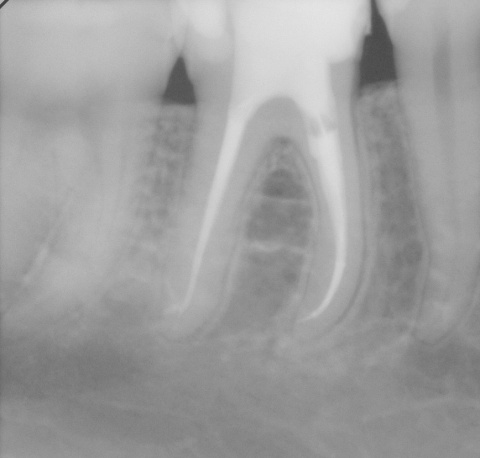

Durch eine Vielzahl von Studien konnte belegt werden, dass die Versorgung mit implantatgetragenem Zahnersatz eine bewährte Behandlungsoption darstellt. Gleichwohl zeigen viele Studien jedoch, dass – wie bei allen Therapiemaßnahmen auch – Komplikationen auftreten können. Diese haben im Allgemeinen biologische oder technische Ursachen. Als häufigste biologische Komplikation findet man die Mucositis (Abb. 1), die Entzündung der periimplantären Gewebe ohne Beteiligung des Alveolarknochens. Nach aktuellen Studien weisen ca. 30 % aller Implantate nach fünf Jahren eine Mucositis auf. Kommt es darüber hinaus zu einer Beteiligung des Alveolarknochens, liegt eine Periimplantitis vor (Abb. 2). Sie tritt nach fünf Jahren bei etwa 10 % der inkorporierten Implantate auf und ist durch den Verlust des periimplantären Alveolarknochens gekennzeichnet. Die Periimplantitis kann, je nach Schweregrad, zum kompletten Implantatverlust führen. Bei einem strategisch wichtigen Implantat kann daraus der Verlust der gesamten prothetischen Versorgung resultieren und eine operativ sowie finanziell aufwendige Neuversorgung erforderlich werden (Abb. 3).